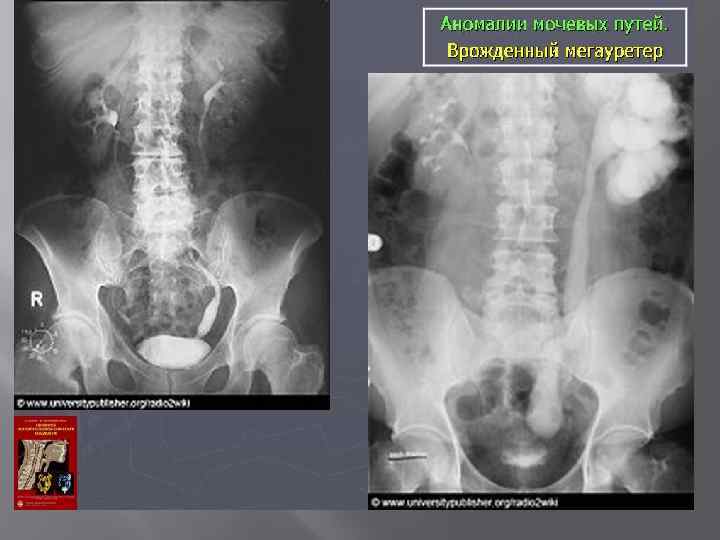

Аномалии развития мочевых путей 1. Количества Аплазия Гипоплазия Удвоенная почка Третья добавочная почка Расщеплённый моч-ник Полное удвоение моч-ника

3. Структуры Поликистоз Солитарные кисты 4. Мочеточника Ахалязия Уретероцеле Ретроковальный